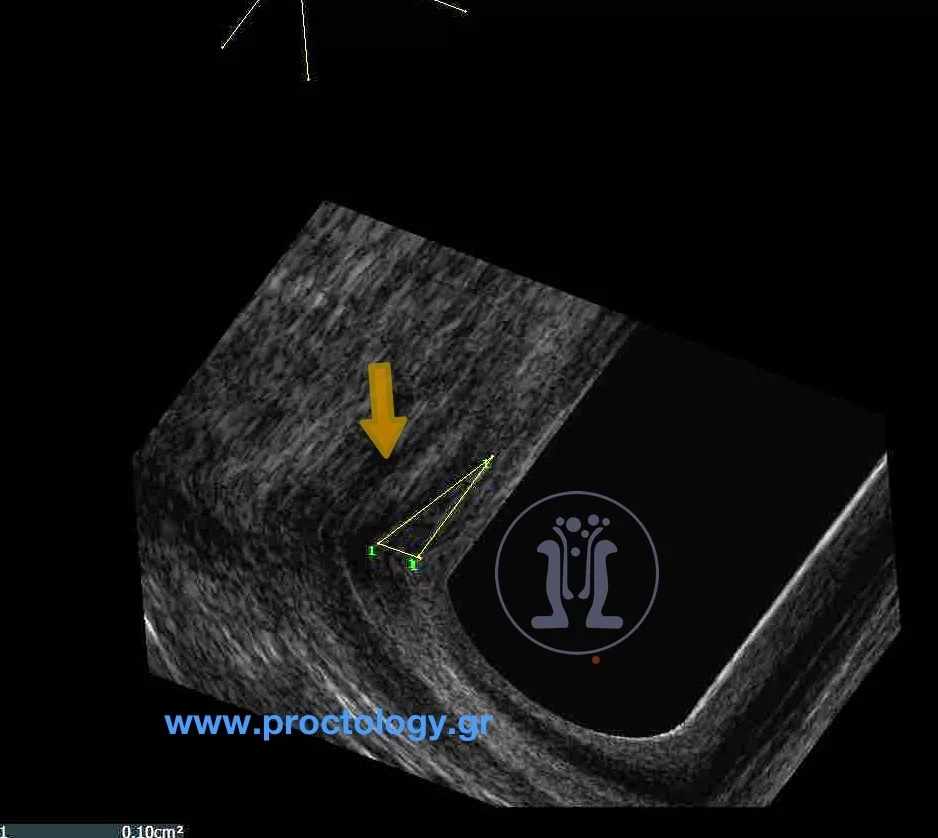

Περίπτωση ασθενούς με ακράτεια στα αέρια και συρίγγιο μετά από εγχείρηση νεαροποίησης ραγάδας με laser. Φαίνεται σαφώς το στόμιο του συριγγίου και στο ενδοπρωκτικό υπερηχογράφημα η διατομή του έσω σφιγκτήρα που προκαλεί ακράτεια στα αέρια.